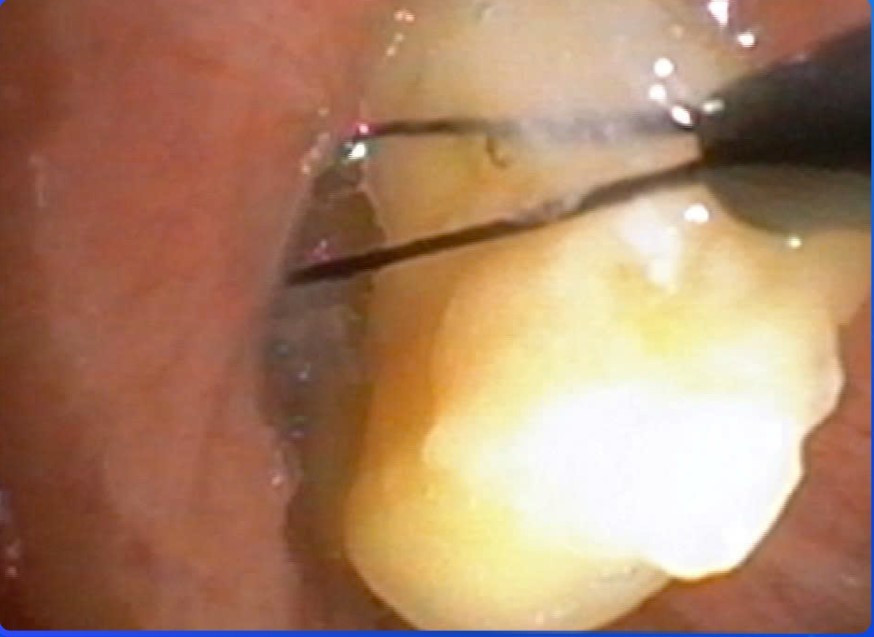

Nội soi lấy hạt ngô gây tắc đường thở cho bệnh nhân - Ảnh BVCC

Người bệnh được chuyển thẳng vào Đơn vị Nội Soi, tiến hành nội soi phế quản ống mềm cấp cứu dưới gây mê. Qua nội soi, các bác sĩ phát hiện nhiều hạt bắp mắc kẹt trong phế quản, gây bít tắc đường thở và là nguyên nhân trực tiếp dẫn đến suy hô hấp. Bằng các dụng cụ chuyên dụng, ê-kíp đã gắp thành công dị vật, giải phóng đường thở cho người bệnh.